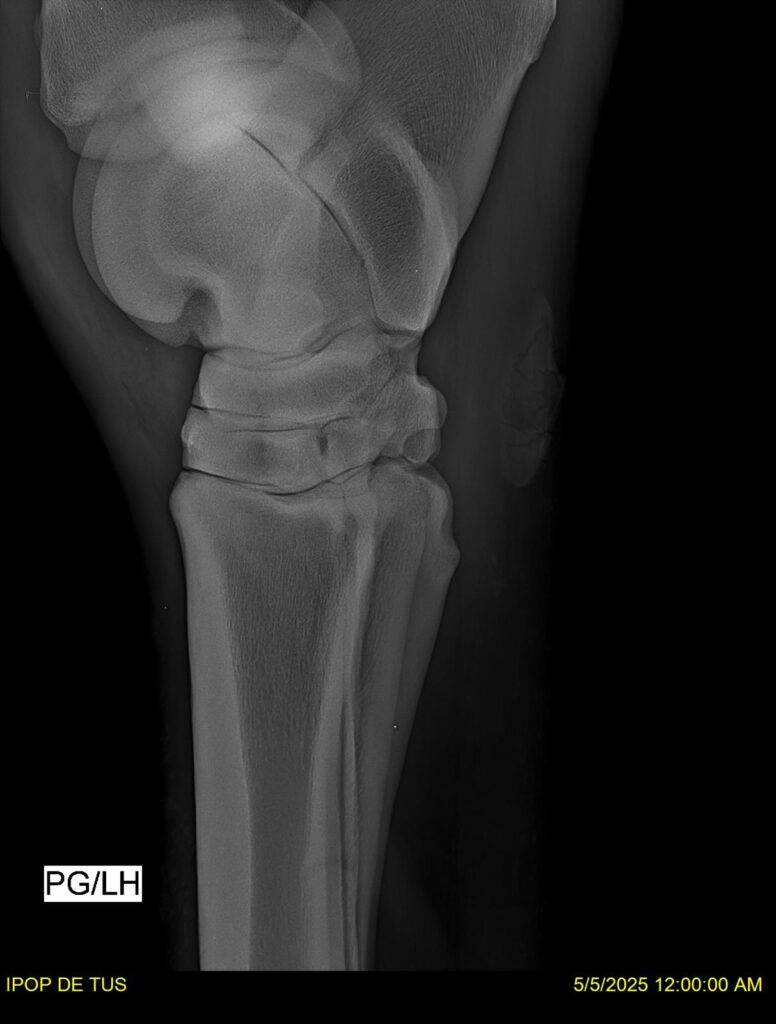

IPOP DE TUS, selle français, hongre, prendra 8 ans en 2026. LIFESTYLE x EROTICBLUS MONTOIS. Sans faute sur 125 et 130. Gentil cheval, respectueux avec des moyens et de la force. Transport OK, maréchalerie OK (pieds nus), santé RAS, Bilan clichés radios + clinique OK.

RADIOS ET CLINIQUE